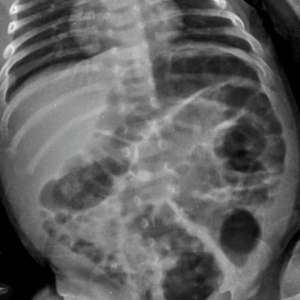

A criança, um menino, apresentava além de vários hematomas e escoriações pelo corpo, em exames aprofundados se constatou lesões ósseas em uma das tíbias, em um antebraço, além de costelas.

Laudo Médico apontou ainda que tais ferimentos expuseram o menino a risco de vida.